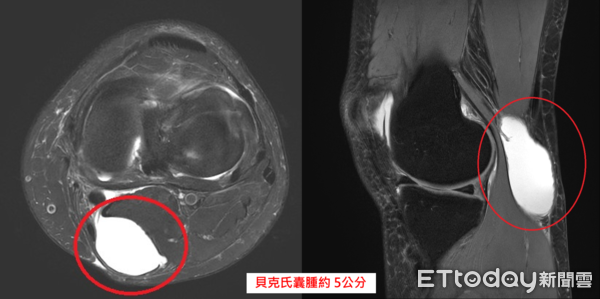

▲女子膝窩長出腫塊,就醫確診是膝蓋積水造成的「貝克氏囊腫 」。(圖/中醫大新竹附醫提供)

若貝克氏囊腫長期存在或反覆發作,可評估以抽吸方式暫時緩解症狀;如囊腫持續變大,甚至使行走、蹲跪不便,或壓迫周邊血管與神經,出現麻木感或循環不良,則不宜再拖延,應考慮手術治療,例如前述患者,經影像檢查確認為大小約5公分的貝克氏囊腫後,因已影響生活功能,決定進行微創膝關節鏡手術,手術時間約30分鐘,隔天即可下床活動,2天後順利出院。